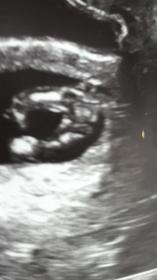

I know 12 weeks is really early but I'd still love your input! Attachment 34902Attachment 34902Attachment 34903

Too early for me to guess, my little boy looked like this at 12 weeks, I swayed for a girl so it gave me false hope. I have seen potty shots at this gestation where the penis and scrotum were visible. If you pushed me I would say it looks girlie at this stage but much too early. What are you hoping for? X

Maybe girl, but I agree with Girlieplease, it's very early and could be boy.

I'd like to say girl due to the three lines but it's not fully developed there yet so very hard to tell!

Looks like my girls. Congratulations